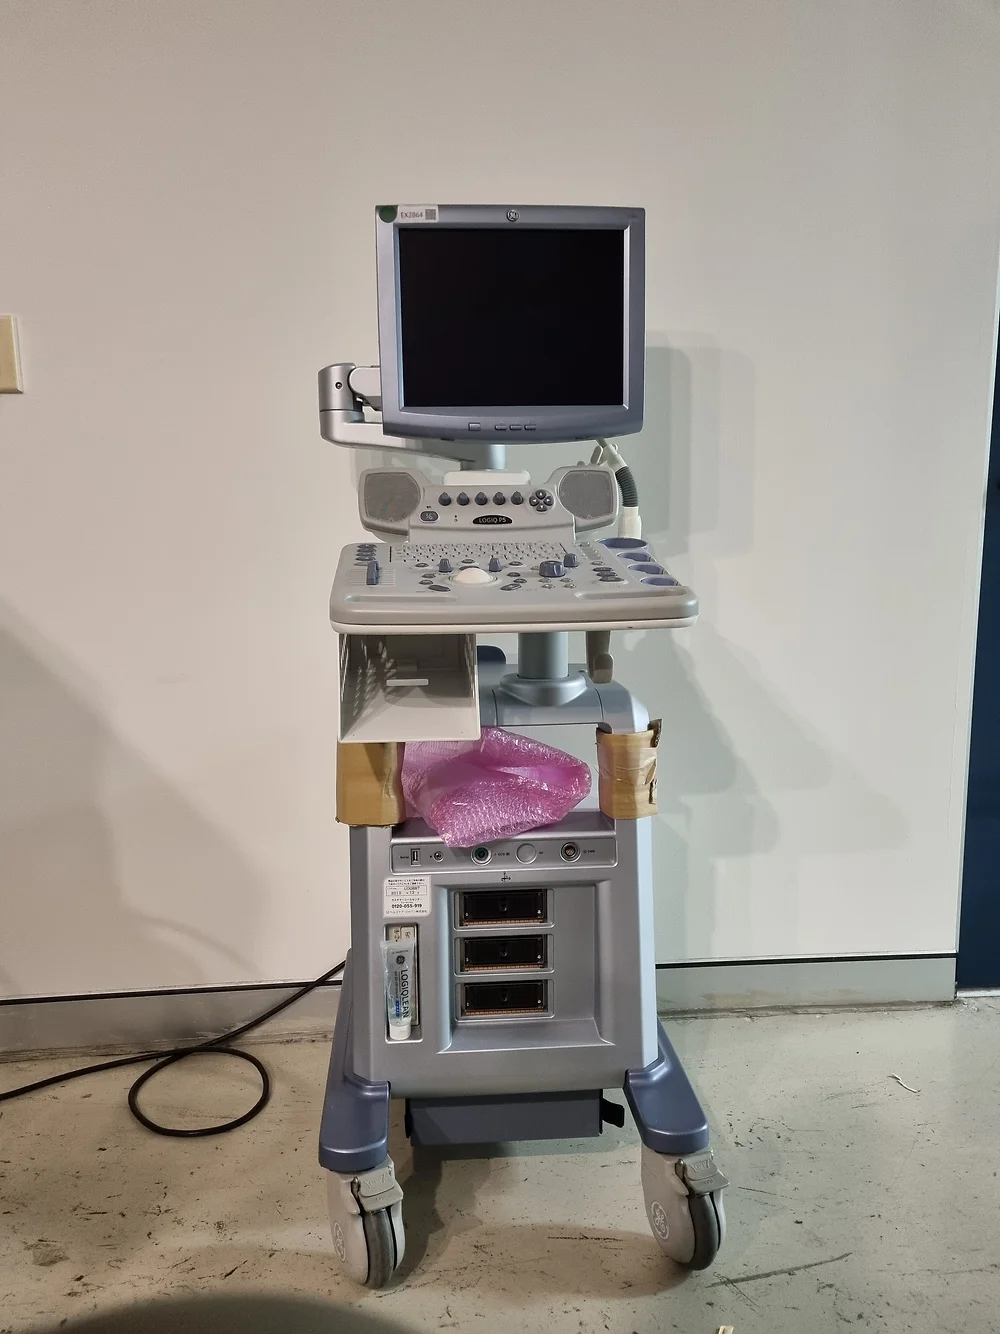

Logiq 7_BT07

Description

Elevate Your Imaging Experience with the GE Logiq 7 Ultrasound Machine

Unleashing Precision and Versatility: Introducing the GE Logiq 7

The GE Logiq 7 ultrasound machine stands as a pinnacle of versatility and reliability, catering to a myriad of clinical needs while delivering exceptional imaging quality through cutting-edge 3D technology and an array of enhanced imaging features.

Cutting-Edge Technology for Superior Imaging:

- Advanced Imaging Capabilities: Experience unparalleled image clarity and precision with the Logiq 7’s 3D technology and a comprehensive suite of imaging features, including Power Doppler Imaging, M-Mode, and Color Flow Mode (CFM).

- User-Friendly Design: Designed with user comfort and efficiency in mind, the Logiq 7 features a intuitive touch-screen interface and ergonomic construction, ensuring ease of use for clinicians during diagnostic procedures.

- Seamless Data Management: Benefit from convenient image archiving options, including storage to CD, MOD, or hard drive, enabling efficient data management and access to diagnostic records.

Versatile Clinical Applications:

- Wide Range of Clinical Applications: From abdominal and OB/GYN to small parts, pediatric, vascular, and cardiac diagnostic testing, the Logiq 7 supports a full spectrum of clinical applications, making it a versatile solution for diverse healthcare settings.

Compatible Ultrasound Probes and Transducers:

- Tailored for Every Need: The Logiq 7 is compatible with an extensive range of ultrasound probes and transducers, including phased array, convex array, linear array, endocavity, intraoperative, and volume transducers, ensuring optimal performance across various imaging scenarios.

Experience the pinnacle of ultrasound technology with the GE Logiq 7. Whether you’re conducting routine diagnostic scans or advanced imaging procedures, trust in the Logiq 7 to deliver unmatched precision, reliability, and versatility for all your clinical needs.

Contact us today to discover how the GE Logiq 7 ultrasound machine can elevate your imaging capabilities and transform patient care.